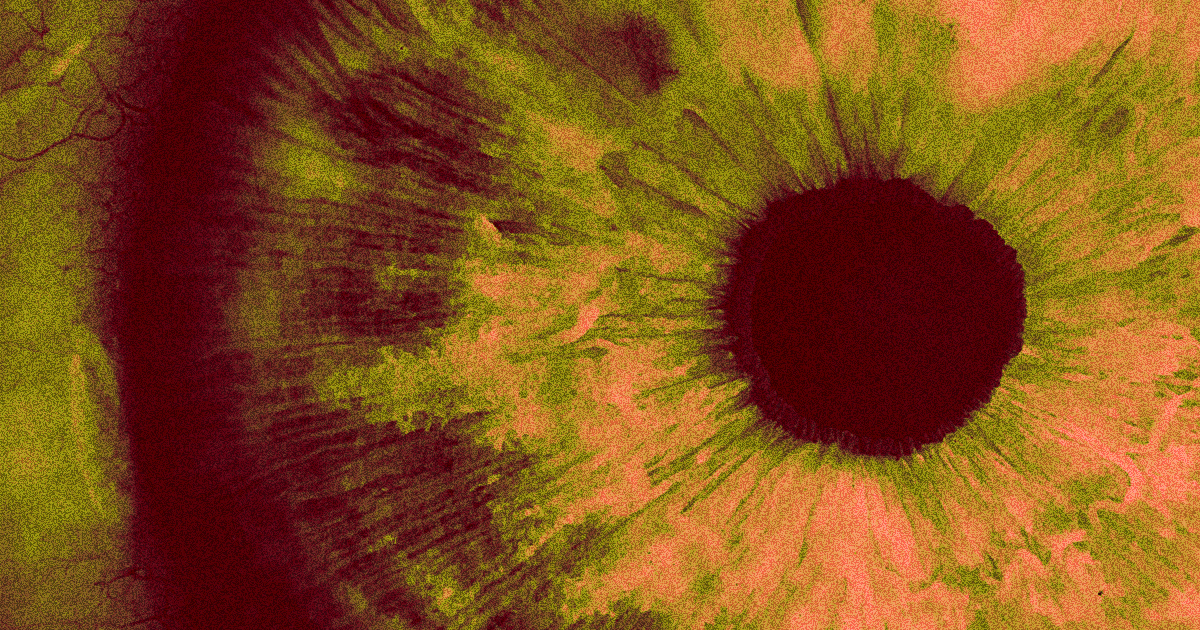

The mutation behind Leber congenital amaurosis prevents cells from producing the CEP290 protein, which is crucial for the eye’s photoreceptor cells. The treatment sneaks RNA into those cells and triggers CEP290 production, essentially reversing the mutation for months at a time.